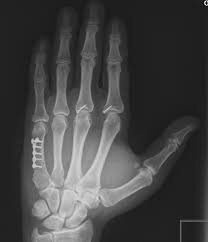

• Sistema radiográfico de Levinshon

Sistema radiográfico de Levinshon

Consiste en la medición efectuada sobre radiografías de falanges de metacarpio y metatarso. Tiene dos inconvenientes importantes: la variaciones óseas de acuerdo a la edad y que se trata de un sistema que demandaría el empleo de un material excesivamente costoso.